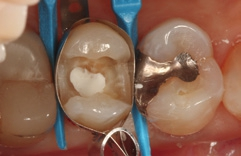

Bei der 55-jährigen Patientin imponierte eine okklusal penetrierte Sekundärkaries an dem Goldinlay an Zahn 15 (Abb. 8). Nach Aussage der Patientin war der Zahn seit ein paar Wochen aufbissempfindlich; die Vitalität war gegenüber Zahn 14 und 16 reduziert. Hieraus ergab sich die Behandlungsindikation zur Entfernung des Inlays und zur Vorbereitung einer endodontologischen Therapie. Nach der Entfernung des Inlays imponierte ein massiver Kariesbefall im gesamten Kavitätenbodenbereich (Abb. 9). Nach der Exkavation zeigten sich eine Verbindung zur Pulpa als auch diverse Infraktionslinien (Abb. 10). Die Verbindung zur Pulpa wurde interimsmäßig überkappt (TheraCal LC, Abb. 11); die Trepanation des Zahnes wurde dem Endodontologen überlassen. Vor einer endodontologischen Behandlung ist eine dichte adhäsive präendodontologische Aufbaufüllung essenziell. SDR flow+ hat die Indikation zur Aufbaufüllung in seinem Indikationsspektrum.